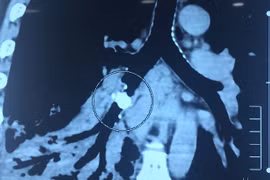

(GLO)-Các bác sĩ Khoa Ngoại Tổng hợp (Bệnh viện Đa khoa trung tâm tỉnh Gia Lai) vừa phẫu thuật thành công cho bệnh nhi N.H.G.H (11 tuổi, ở xã Tuy Phước Tây) bị viêm phúc mạc do dị vật xương cá gây thủng ruột.